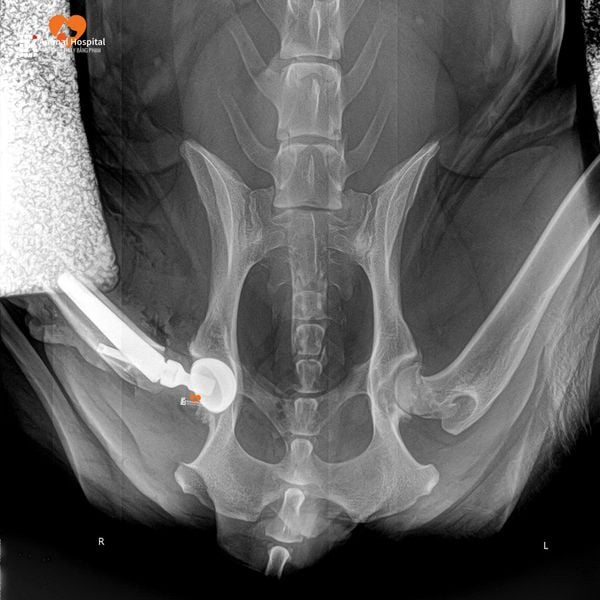

Dịch Vụ Thay Khớp Háng Nhân Tạo (Total Hip Replacement – THR)

Dưới sự phụ trách chuyên môn của Giám đốc Phạm Bằng – được chứng nhận chính thức trong phẫu thuật Thay Khớp Háng Toàn Phần của BlueSAO cho chó và mèo (Total Hip Replacement – THR), bệnh viện áp dụng kỹ thuật chỉnh hình tiên tiến hàng đầu thế giới nhằm điều trị hiệu quả các bệnh lý nặng ở khớp háng như thoái hóa, trật khớp bẩm sinh hoặc gãy cổ xương đùi.

Phẫu thuật THR cho thú cưng là kỹ thuật đòi hỏi trình độ cao, hệ thống thiết bị hiện đại và đào tạo bài bản theo chuẩn quốc tế. Với nền tảng vững chắc trong ngoại chấn thương chỉnh hình thú y và chứng chỉ quốc tế sau khóa đào tạo THR, anh Bằng đã thực hiện thành công nhiều ca thay khớp háng toàn phần, giúp các bé thú cưng giảm đau, phục hồi vận động và nâng cao chất lượng sống.

Hàng năm, anh Bằng vẫn tiếp tục tham dự các khóa đào tạo và hội thảo chuyên sâu quốc tế về THR, nhằm cập nhật những cải tiến mới nhất trong kỹ thuật và công nghệ phẫu thuật – đảm bảo mỗi ca mổ đều đạt độ chính xác và an toàn tối đa.